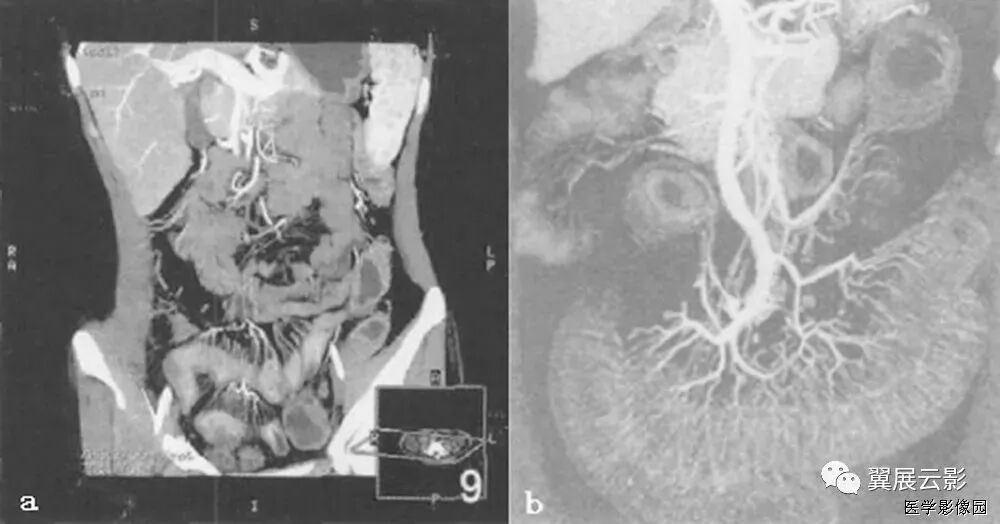

13、三明治征 (夹心面包征或夹心饼征)

指2个均质软组织肿物组成三明治面包,系膜脂肪和管状物为构成夹心,是腹部CT横断扫描时的影像表现。系膜脂肪和血管组成夹心,肿大淋巴结组成面包;在给予增强剂后系膜管状结构(血管、肠管)相对脂肪增强,夹心层突出。因为淋巴结增大会压迫血管,阻碍静脉回流,使夹心层内增强的血管更加明显。

当经静脉及口服造影剂后,肠系膜血管结构较脂肪明显强化,从而可使夹心更加突出。导致肠系膜淋巴结肿大的病因很多。除淋巴瘤外,癌、肉瘤、类癌、获得性免疫缺陷相关性淋巴结增生综合征、结核、肠源性脂肪代谢碍及炎症性肠病等也是最常的病因。

三明治征为肠系膜淋巴瘤的特异征象。因为只有在肠系膜淋巴瘤中淋巴结才可以长得很大,并包绕脂肪、肠管和血管而不产生任何临床症状。肠系膜淋巴瘤偶尔可侵犯浆膜及固有肌层,有时会引起小肠出血但极少引起游离性穿孔。肠系膜淋巴瘤还可以引起腹膜后淋巴结肿大。

总之,三明治征指的是CT横断面上,巨大增生的肠系膜淋巴结包绕肠系膜脂肪和血管而形成的类似三明治的影像。对于没有移植病史的患者,非霍奇金淋巴瘤是三明治征的主要病因;有移植病史的患者,产生三明治征的原因则可能是淋巴组织增生性疾病,随着接受移植手术的患者不断增多,三明治征可能会在临床上越来越常见。

图1:非何杰金淋巴瘤患者口服造影剂后增强CT横断面。显示2个巨大系膜淋巴肿物(2个面包-带尾箭头),包绕中心系膜和增强的血管。注意增强的小肠位于周边,腹膜后淋巴结显著增生-箭头)。

图2:患者6个月前曾行左肾移植发现PTLD,血管和口服造影剂横断CT显示三明治征——系膜淋巴肿物(实心带尾箭头),靠近右肾(箭头),有腹膜淋巴结肿大(空心带尾箭头)。